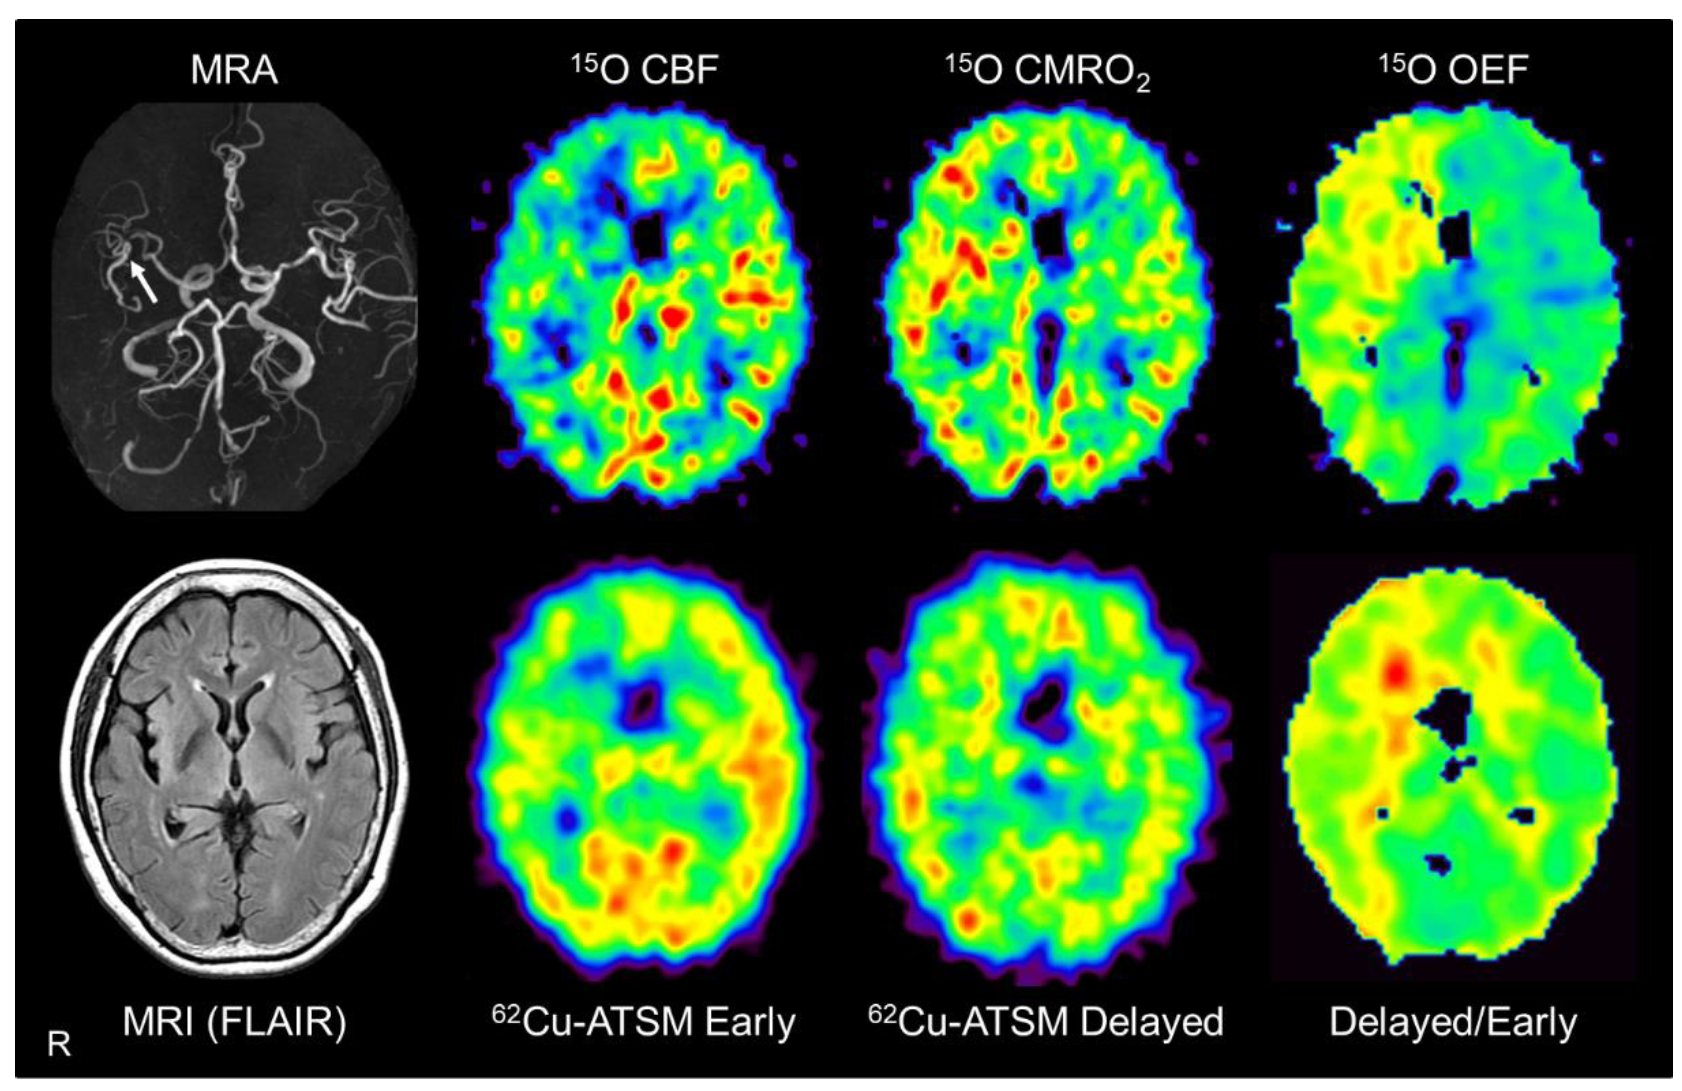

7. Application of 62Cu-ATSM PET to Cerebrovascular Diseases

7.1. Pathophysiological Changes in Brain Misery Perfusion

7.2. PET Imaging in Patients with Misery Perfusion